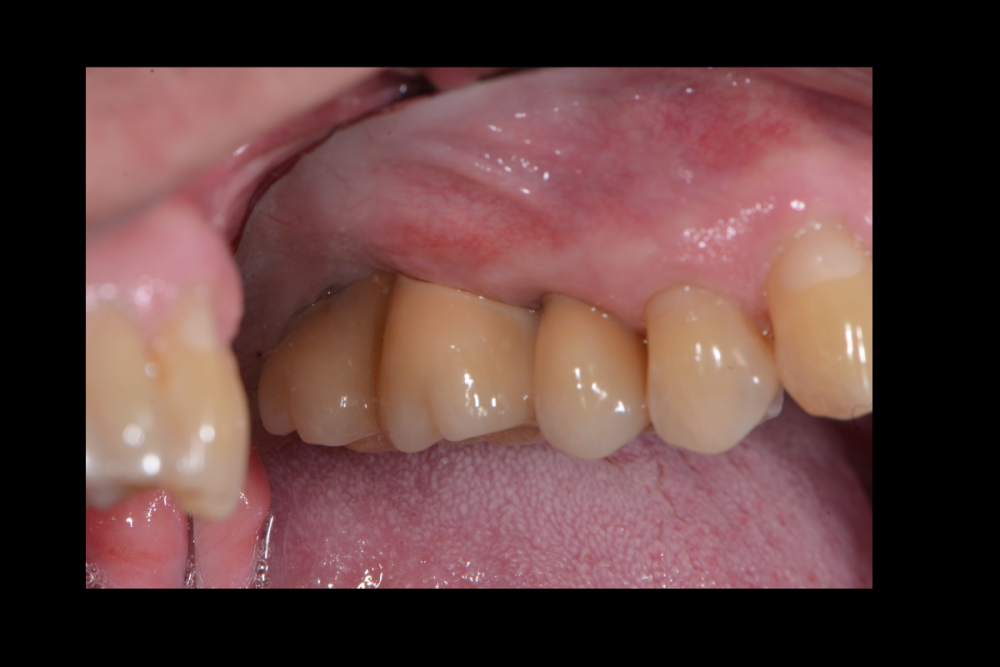

Карен Аванесов Опубликовано 31 января, 2022 Автор Поделиться Опубликовано 31 января, 2022 10.05.2021 в 15:42, It'sGeorgy сказал: Если есть фото и снимок после протезирования, добавьте пожалуйста. 1 1 Ссылка на комментарий

Карен Аванесов Опубликовано 10 мая, 2021 Автор Поделиться Опубликовано 10 мая, 2021 17 минут назад, It'sGeorgy сказал: Если есть фото и снимок после протезирования, добавьте пожалуйста. Правильно ли я понимаю, что у дистального имплантата мультиюнитом выход шахты будет как раз посередине 1.7? Что думаете о таком концепте? (взял со Штраумянского недавнего онлайн-форума) Фото покажу позже. Да, возможно так и будет. Очень здорово что Вы смотрите такие онлайн-форумы, наверно поучительно. Моей работе на слайде 7 лет, хирургия и ортопедия моя, зуботехническая работа такая как есть, фиксация цементная, на дистальном имплантате индивидуальный титановый абатмент, тем не менее нет каких либо проблем. Близкое расположение имплантатов, в данном случае рентгенологический артефакт. Пациентке было с чем сравнивать ощущения, слева делал открытый синуслифтинг, гуманный подход он лучше для пациента и оператора, на мой взгляд. 2 1 2 Ссылка на комментарий